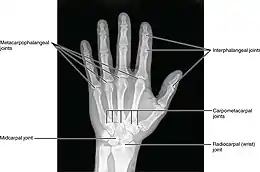

The diagnosis is based on a clinical presentation, molecular analysis, electropherogram and radiograph.[10][11][4] This disease is diagnosed within the first few years of life.[4] Identification of the main characteristics is the key factor in diagnosis. Molecular analysis is used to examine the DNA of the affected person and their parents.[10] For this, a blood sample is needed and the DNA will be extracted with an automatic DNA extractor.[10] The results will show the mutated chromosome and identify if this chromosome was passed on from a parent.[10] A radiograph will show abnormal growth plates and misshapen bones in the limbs.[7][3][10] This can confirm the abnormal development and premature fusion of the regions where the diaphyses, of certain long bones, meet their epiphyses.[4] Electropherogram is used to identify genotyping.[12] These results can be used to compare to a normal sequence and relatives sequences.[13]